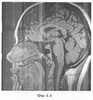

На фиг.2 представлены магнитно-резонансные томограммы вариантов гипофиза, полученные во фронтальных сечениях. При этом на фиг.2а показан гипофиз в узком турецком седле; 2б – круглый гипофиз в косом турецком седле; 2в – корытообразный гипофиз в косом турецком седле; 2г – гипофиз с уменьшенным правым крылом; 2д – гипофиз с заостренными краями; 2е – гипофиз с закругленными краями; 2и – гипофиз в узком турецком седле; 2ж – гипофиз в косом седле; 2з – корытообразный гипофиз в косом седле; 2к – гипофиз с уменьшенным правым крылом; 2л – гипофиз с приподнятыми крыльями; 2м – гипофиз в пустом турецком седле.